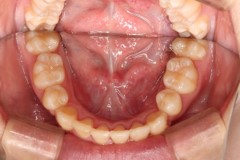

ご相談時